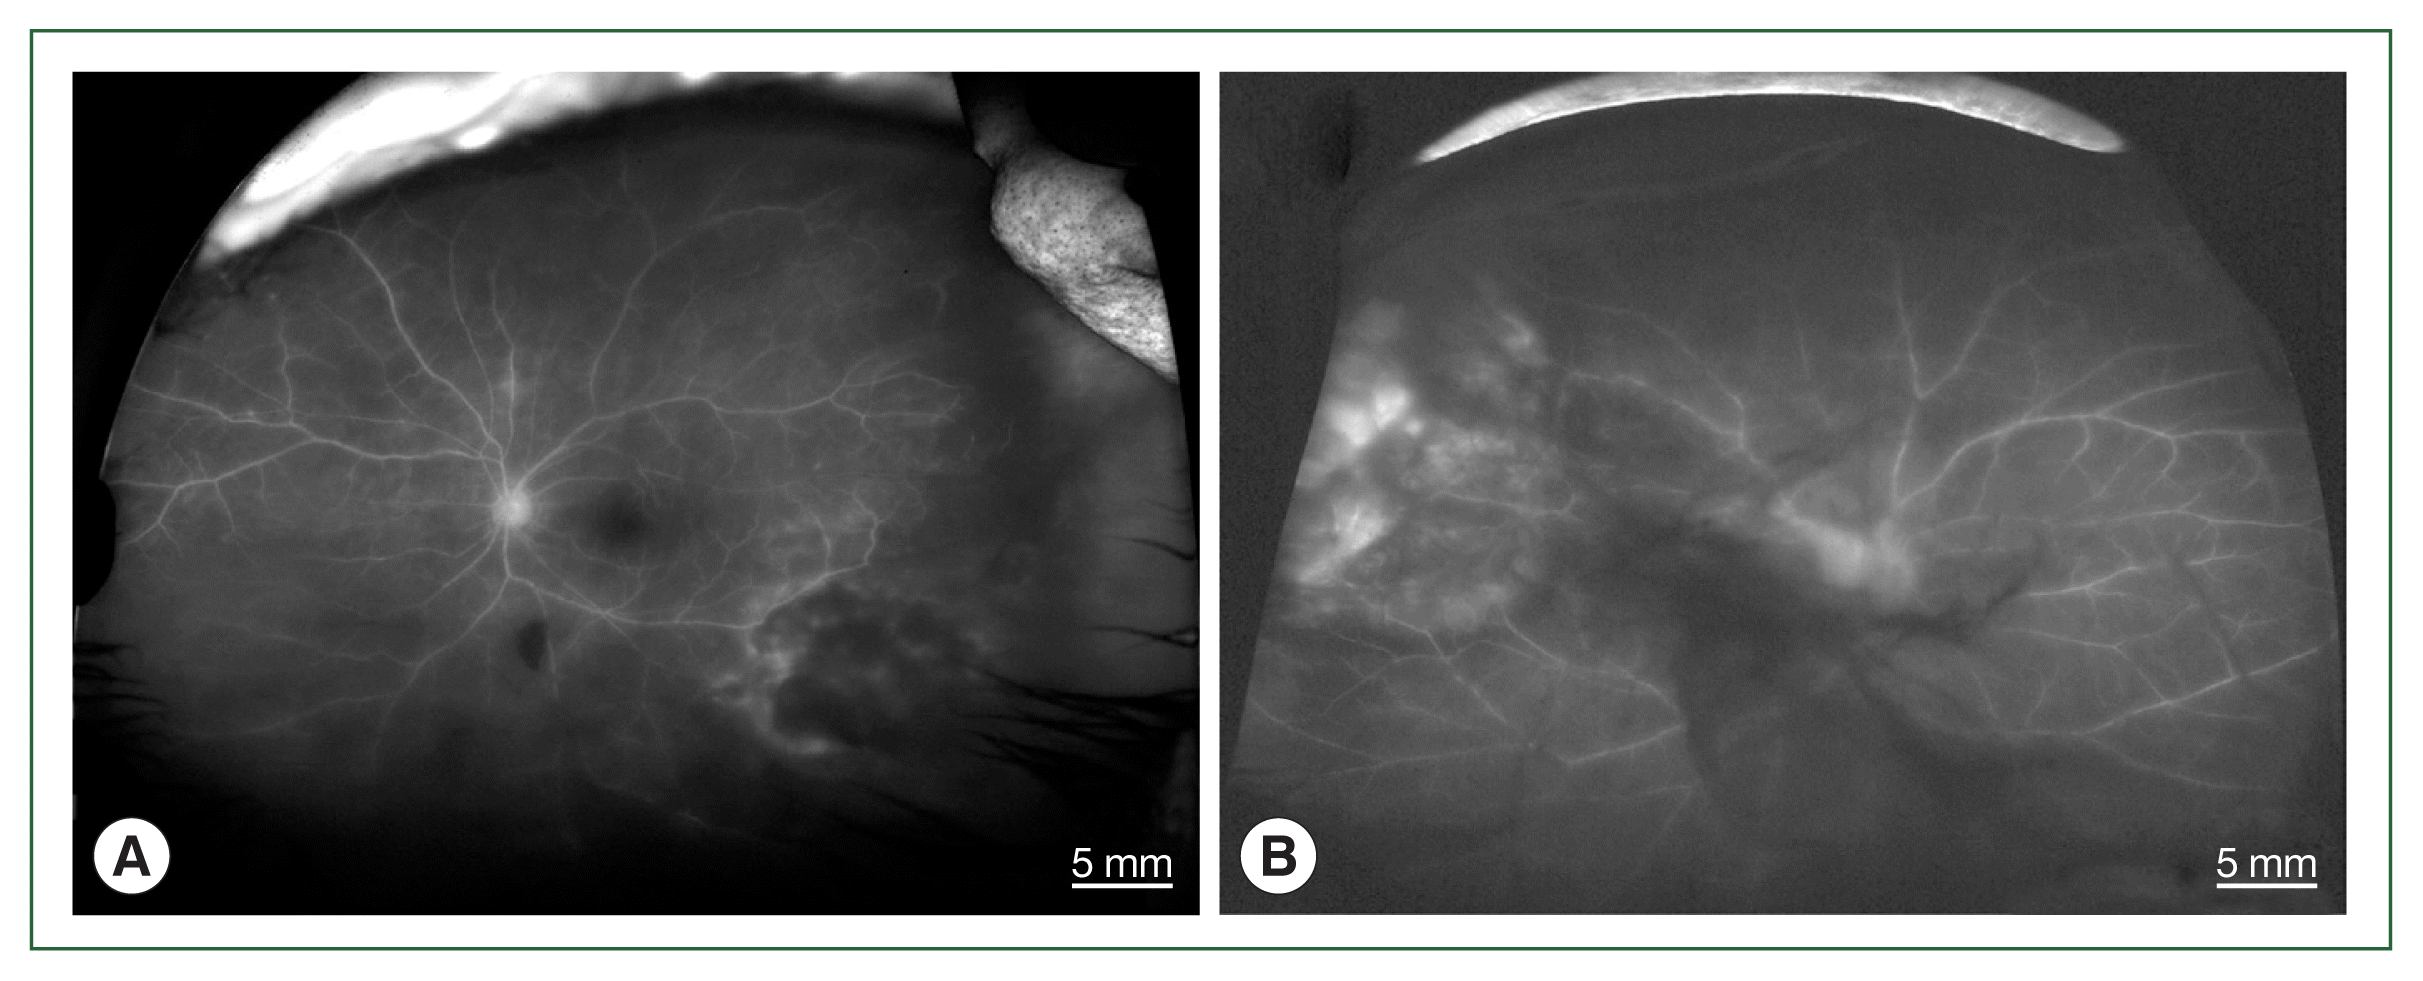

The 4 patients presented persistent unilateral visual disturbance 2–3 months before assessment. The ocular examination revealed that all study patients also exhibited unilateral panuveitis. Two patients (cases 1 and 2) did not show signs of chorioretinal scars, while the other 2 patients (cases 3 and 4) had preexisting scars on the retina and choroid. All of them showed an initial decimal visual acuity between 0.1 and 0.5. The ophthalmic analysis also revealed active retinochoroiditis in the 4 patients (Fig. 1) and papillitis and periphlebitis in cases 1 and 4, which were more evident by fundus fluorescein angiography (Fig. 2). All study patients also exhibited vitritis and anterior uveitis. Three patients (cases 1, 3, and 4) who underwent vitrectomy for diagnostic and therapeutic reasons had negative cytology for lymphoma cells. The remaining patient (case 3) had re-vitrectomy combined with scleral encircling for total retinal detachments developed later (Fig. 3). Only 1 patient (case 1), who was previously diagnosed with acute retinal necrosis (ARN) in a local ophthalmology clinic, received a systemic steroid treatment (60 mg per day) for posterior uveitis before visiting the Eye Center at the Seoul St. Mary Hospital, Catholic University. None had received any medication (including antibiotics) before the examination.

Fig. 2

Fundus fluorescein angiographs of papillitis and vasculitis in an ocular toxoplasmosis patient; (A) left eye of case 1, (B) right eye of case 4.